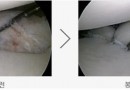

석회화 건염

어깨 힘줄에 석회가 생기는 질환으로 일단 석회가 생기면 통증이 대단히 심한 것이 특징입니다. 통증이 심해서 밤에 잠을 이룰 수 없는 정도로 돌의 크기는 갖가지 모양으로 다양합니다. 여러 개가 한꺼번에 생기는 경우도 있으며 발생원인은 힘줄에 퇴행성 손상이 생기고 …